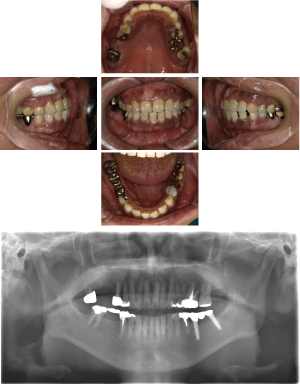

60代 女性 全顎 インプラント サイナスリフト等

| 年代・性別 | 60代・女性 |

| 主訴 | 上顎の入れ歯が割れた。リンゴやおかきを食べられるようになりたい。 |

| 部位 | 右上④3②・左上②3④5⑥のブリッジ |

| 治療期間 | 2年 |

| 費用 | ¥2,447,500(税込) |

| 副作用・リスク |